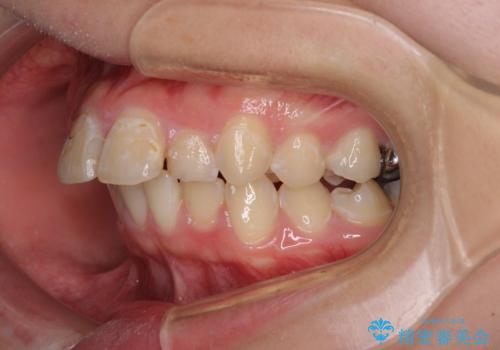

- 上の前歯の出っ歯とでこぼこの歯並びを気にして来院された患者様です。

上下顎歯列ともに前方に突出していましたが、上顎歯列がより前方位にあったため、上顎左右は第1小臼歯を、下顎左右は第二小臼歯を抜歯することとしました。

目立たないワイヤー装置にて抜歯矯正を行うこととしました。